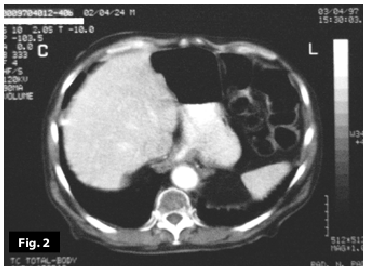

Figure2

Figure1-2